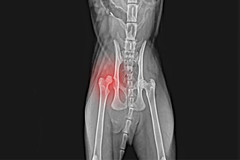

Khi chó mèo không may gặp tai nạn gây ra hiện tượng xương đùi chật ra khỏi ổ khớp xương hông sẽ gây ra hiện tượng đau đớn cho chúng. Hiện tượng này sẽ làm cho chó mèo không thể đi được bình thường bằng bốn chân. Do vậy phẫu thuật là giải pháp giúp chúng thoát khỏi tình trạng đau đớn và có thể đi được bằng 4 chân.

Bác sĩ sẽ cắt bỏ phần đầu và cổ của xương đùi